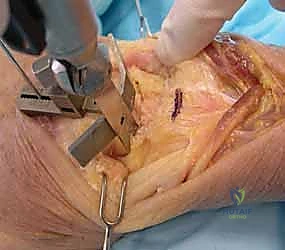

A longitudinal dorsal incision, positioned slightly radial to the midline, is made extending from approximately 4 cm proximal to the radiocarpal joint down to the midpoint of the third metacarpal shaft. Sharp dissection is carried down through the subcutaneous tissues to the level of the extensor retinaculum, taking meticulous care to identify and protect the sensory branches of the superficial radial nerve and the dorsal sensory branch of the ulnar nerve. The third dorsal compartment is opened, and the extensor pollicis longus (EPL) tendon is exposed, mobilized, and retracted radially. The retinaculum is then elevated as a continuous flap. The radial wrist extensors (ECRL and ECRB) are exposed and mobilized radially, while the first compartment tendons are mobilized from the distal radius and protected. The tendons of the fourth and fifth compartments are mobilized ulnarly, ideally without opening their respective synovial compartments to prevent postoperative adhesions.

With the extensor tendons mobilized and safely retracted, a longitudinally based capsulotomy is performed. The capsule is reflected as radially and ulnarly based full-thickness flaps, exposing the distal radius and the entire carpus down to the base of the third metacarpal. Preparation of the distal radius involves scoring a reference line to ensure the DRUJ is preserved. The radial canal is sequentially broached to accept the modular radial stem. The modular radial stem component is designed to fill the distal radius canal to prevent loosening and provide rotational stability. While approved for implantation with bone cement (PMMA), most modern wrists are implanted with press-fit, cementless fixation to encourage osteointegration. Cement is generally reserved for cases of significantly compromised bone stock, severe osteopenia, or revision scenarios.

Following capitate reaming, the chosen carpal plate and stem are assembled and inserted into the capitate and seated onto the resected carpal surface. The carpal plate is anchored to the carpus with a radial screw that optimally does not penetrate the second metacarpal, and a second screw placed ulnarly into the hamate. This construct ensures stable distal fixation while avoiding the deleterious lever arm of a long metacarpal stem. Trial reductions are performed to assess stability, range of motion, and impingement. Once kinematics are confirmed, the definitive ultra-high-molecular-weight polyethylene (UHMWPE) body—which is direct compression molded onto a cobalt chrome alloy radial body—is impacted. The capsule and extensor retinaculum are meticulously repaired to prevent extensor tendon bowstringing and provide a robust soft tissue envelope over the implant.